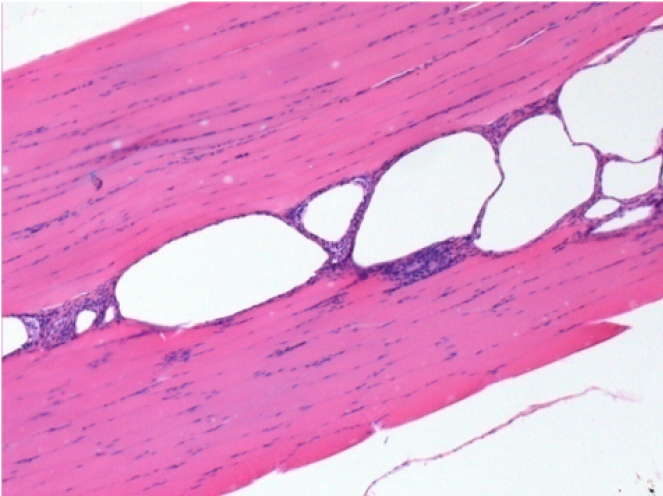

7 months (D210)after Endopeel IM Injection 0.1ml in the right pretibial muscle.

Complete Restitutio ad integrum after 7 months

L :Control 50xD210

R50X-D210